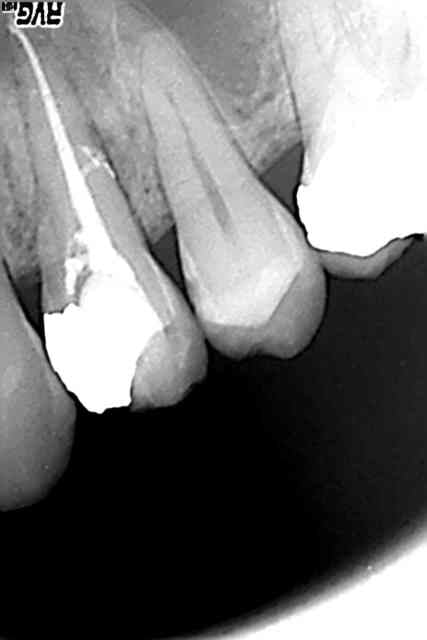

desole pour le retard mais je vois que certains restent connectes en permanence ;la technique a ete decrite sur la revue d endo vol 17 num 4 dec 98:

apres une preparation du canal au protaper,un maitre cone est ajuste a la longueur de travail -0,5 mm puis condense lateralement avec un speader en titane à l t -2mm;une compaction a chaud est ensuite realisee avec

un condenseur niti sur lequel on a enduit de la gutta basse viscosite chaude identique a celle du cone de gutta(obturation homogene )

c est une technique rapide et fiable dont la seule limite est a mon avis les canaux larges et ouverts a l apex

Le systeme microseal demande qd meme une periode d adaptation, l gutta est moins radiopaque, il y a souvent des bulles si on ne maitrise pas parfaitement la methode, casse de compacteur etc...

Int Endod J. 2003 Dec;36(12):876-82. Related Comparison of MicroSeal and System B/Obtura II obturation techniques.

Le système micro seal (identique au endomagic), perd de son intérêt si tu utilises des cones "souples" comme les cones Protapers, très faciles à ramollir au gutta condensor.

je pense qu 'amener de la gutta chaude donc deja ramollie via le condenseur souple en titane (systeme miro seal ) amene un plus dans la compaction et l obturation tridimensionnelle du canal